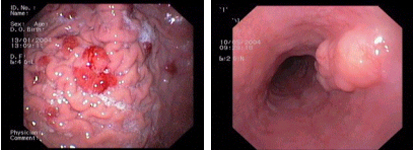

imagen4

Hiperplàsia de glàndules fúndiques a l'estómac, una patologia freqüent de caràcter benigne